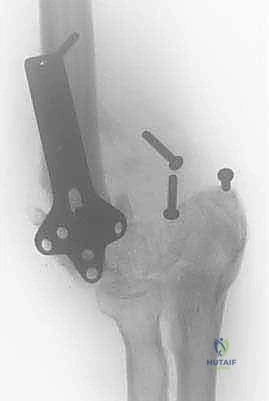

| الأشعة السينية العادية (X-Rays) | تقييم الهيكل العظمي الأساسي، الكشف عن الكسور القديمة، المسامير والشرائح السابقة، ومدى تآكل المفصل. | كخطوة أولى وأساسية في جميع الحالات. وتؤخذ من زوايا متعددة. |

| الأشعة المقطعية (CT Scan) مع بناء ثلاثي الأبعاد 3D | توفير تفاصيل دقيقة للغاية عن شكل العظام، التكلسات المغايرة، التئام الكسور، وتخطيط حجم ونوع المفصل الصناعي أو الشرائح المطلوبة. | ضروري جداً قبل التخطيط لجراحات التبديل الكلي للكوع أو إزالة التكلسات العظمية الضخمة. |